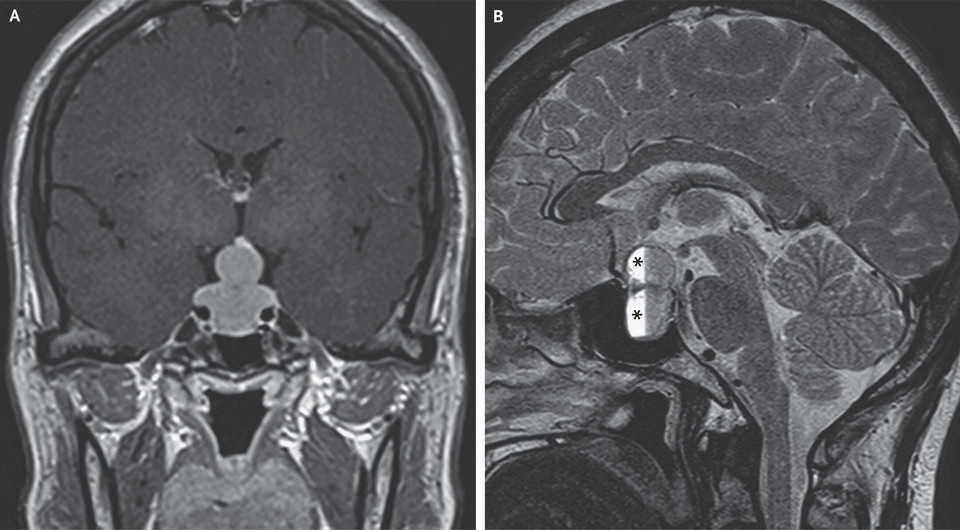

В китайскую неврологическую клинику поступила 47-летняя женщина с жалобами на прогрессирующие головные боли. Они сопровождались размытостью зрения, галактореей и нерегулярными менструациями в течение месяца. При осмотре отмечалось снижение остроты зрения примерно до -1,00 диоптрии при сохранности полей зрения и движений глазных яблок. На МРТ головы был виден увеличенный гипофиз, выпячивающийся из турецкого седла в супраселлярную цистерну мозга и сдавливающий перекрест зрительных нервов. Такая нейрорадиографическая картина, известная как «признак снеговика», возникает, когда медленно растущая опухоль в турецком седле при росте вверх сдавливается между его бугорком и спинкой, образуя перемычку и характерную форму. Кроме того, на снимке было выявлено кровоизлияние в гипофиз. Ювэй Чжоу (Yuwei Zhou) из Народной больницы Вэньчжоу и Вэй Вэн (Wei Weng) из Вэньчжоуского медицинского университета представили этот случай в The New England Journal of Medicine.

Лабораторные анализы показали повышенный уровень пролактина — до 200 нанограмм на миллилитр (при норме 3,3–26,7), а также выявили надпочечниковую недостаточность и гипотиреоз центрального происхождения. На основании обследования пациентке поставили диагноз — пролактинсекретирующая аденома гипофиза (пролактинома) с субклиническим кровоизлиянием в гипофиз. Ей выполнили эндоскопическую транссфеноидальную резекцию опухоли. Симптомы исчезли через три дня после операции, уровень пролактина нормализовался через месяц. На МРТ через год в турецком седле была видна остаточная ткань гипофиза без других структурных аномалий.